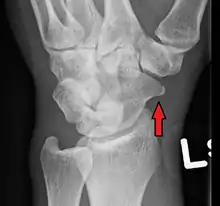

A subtle scaphoid fracture

A more obvious scaphoid fracture on a scaphoid view X ray

Radiolucency around a 12 days old scaphoid fracture that was initially barely visible.[10]